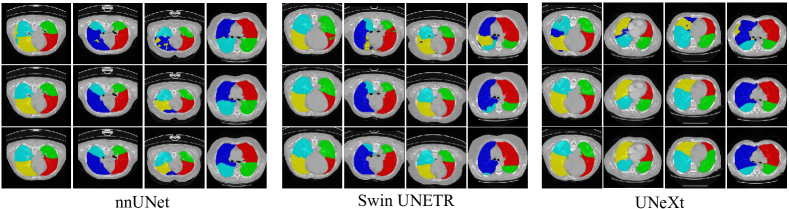

Evaluations on Fused Lung Lobe. To further assess the ability of our model to address boundary confusion, we carried out experiments on the fused lung lobe dataset. Lung lobe CT scans with COVID-19 infections bear uncertain boundaries with noise adjacent to them, which brings a huge challenge for the precise segmentation of inter-class boundaries. Besides, lung lobe CT datasets with COVID-19 infections show a different domain distribution from that of clean lung lobe datasets. Thus, it is more difficult to train a model to implement the segmentation task for the fused lung lobe. Table 2 illustrates the performance comparison between our model and other CNNs and Transformer-based models. We can discover that 3D UNet shows poor segmentation results for the fused lung lobe dataset, which results from the fact that the vanilla structure falls lack of strong representation abilities [87]. Detailedly, Figure 6 reveals that 3D UNet cannot finely localize the boundaries between different parts of lobes. Compared with that, MedNeXt [55] and nnUNet [1] can generate rich voxel-wise features to boost models’ generalization abilities on this multi-domain dataset. Specifically, MedNeXt achieves a Dice score of , a HD95 metric of 7.25mm, an ASSD metric of 1.517mm. As the recent SOTA model, MedNeXt outperforms other models on segmentation metrics for left lobes. However, for right lobes which have a more complicated structure especially on the inter-class boundaries, networks including nnUNet, 3D UX-Net, and Swin UNETR cannot well address the boundary confusion problem. By introducing the pushing and pulling branch into the baseline model, we achieve a Dice increase, 0.69mm HD95 decrease, and 0.200mm ASSD decrease compared with MedNeXt. And it is worth mentioning that PnPNet improves a lot on the metrics for right lobes, with a Dice increase, 2.14mm HD95 decrease, and 0.445mm ASSD decrease. For the right middle lobe with a larger shape variance, our model outperforms nnUNet with a Dice increase, 3.15mm HD95 decrease, and 0.645mm ASSD decrease.

4.4.5 Ablation on plug-and-play Characteristics of the pull-push mechanism

Similarly, we also investigate the plug-and-play Characteristics of pulling and pushing branches. As shown in Table 8, baseline models incorporated with these two branches can achieve better performance on the fused lung lobe dataset, which reveals that the pull-push mechanism bears excellent plug-and-play properties. Specifically, the pull-push mechanism brings significant performance increases for TransUNet and UNeXt, with and Dice increases respectively. More detailedly, the segmentation task on the right lobes can be better solved, which means that pushing and pulling branches are competent to address boundary confusion. Further, we carry out qualitative analysis on the effectiveness of the pull-push mechanism when plugged into other segmentation models. As shown in Figure 13, we select nnUNet [1], Swin UNETR [57], UNeXt [58] from the family of CNNs, Transformer-based and MLP-based models respectively as baseline models. The introduction of SDM and CCM will promote the segmentation precision of inter-class boundary regions, especially in the right lobe.